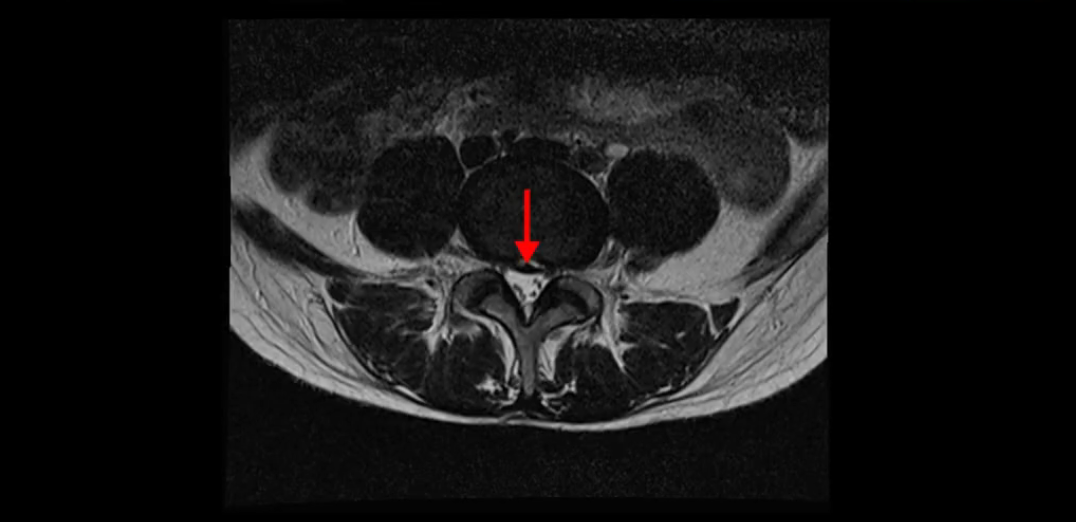

우선 이분의 MRI를 보고 먼저 설명을 드린 후 이런 환자분들의 통증의 원인은 무엇인지, 그리고 치료는 어떻게 해야 하는지 자세히 설명 드리겠습니다.

이분 MRI를 보시면 두 마디의 퇴행성디스크가 있습니다. 그리고 디스크가 조금씩 밀려 나와 있고요. 그런데 디스크 탈출 정도는 두 마디 다 심하지 않습니다. 4번 5번에는 디스크 탈출이 약간 있고,

척추관협착도 약간 진행이 되고 있고요.

5번 1번은 디스크 탈출이 가운데 쪽으로 살짝 있습니다.

또한 양쪽 신경 가지가 빠져나가는 추간공은 매우 넓은 상태입니다.

중요한 것은 이 정도 경미한 탈출과 협착으로는 양쪽 다리가 저리고 아플 수가 없습니다.

그리고 만약에 이 디스크가 급성으로 찢어진 것이라면 아주 심한 디스크성 통증이 있겠죠. 기침이나 재채기를 하면 심하게 아프고 허리를 조금만 구부려도 아주 날카로운 통증들이 생길 겁니다. 그런데 이분은 이런 증상이 전혀 아닙니다. 디스크의 돌출 정도와 협착이 전혀 심하지 않기 때문에 이분이 가지고 계신 양쪽 다리 저림, 특히 이분은 누워있을 때도 양쪽 다리가 저리다고 하는데, 디스크 때문에 그런 증상은 생길 수가 없습니다. 또 이 디스크는 오래된 디스크, 이미 찢어진 섬유륜이 아문 디스크이고, 그러니까 이분은 기침이나 재채기를 못하는 증상이 없는 거죠. 그 다음에 허리를 구부릴 때 뻐근한 증상은 있지만 아주 날카로운 통증은 없습니다.

이처럼 이분의 가벼운 디스크 탈출은 이미 오래 전에 진행되었고 섬유륜 자체는 이미 아문 상태인데도 디스크내장증을 진단받은 환자들 중에는 본인이 섬유륜 파열 환자라고 끝까지 믿는 분들이 많습니다. 다시 말하지만 디스크내장증이라는 진단을 받은 환자들 거의 대부분 섬유륜 파열 증상이 아닙니다. 진단이 잘못되면 어떤 치료를 받아도 좋아질 수 없습니다. 그럼 이분은 다른 여러 병원에서 어떤 얘기들을 들었을까요?

이분 MRI를 보시면 퇴행성디스크가 있고 약간의 협착이 있지만 이 정도의 퇴행성디스크와 협착으로는 신경이 눌려서 양쪽 다리가 저리고 아픈 증상이 나올 수가 없습니다. 그래서 MRI와 이 환자분의 다리 증상이 매치가 안 된다고 하는 의사들이 많은 겁니다.